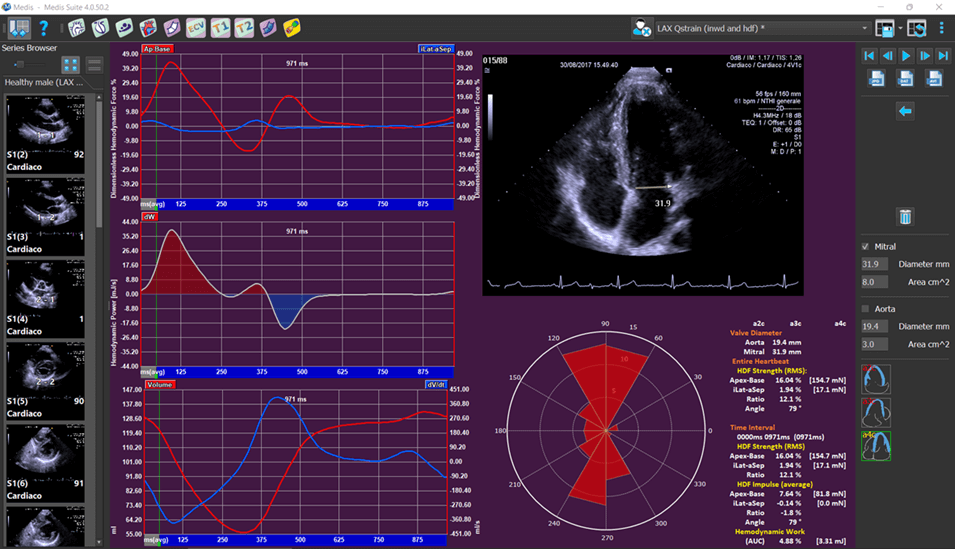

Medis Suite Ultrasound is the latest addition to the Medis Suite portfolio for cardiovascular imaging. Based on 20 years of developments and innovations, we bring you the latest image post-processing tools in advanced cardiac deformation analysis for echo. Medis Suite Cardiac Ultrasound (Echocardiography) is currently available for research use. Medis Suite Ultrasound is a continuation of over 20 years of innovative algorithms and ground-breaking work in Echocardiography software by AMID. AMID was acquired by Medis in 2020.

- Considered by many the gold standard vendor independent software for advanced cardiac deformation analysis, providing deeper insight into heart function

- Allows the quantitative evaluation of the Left Ventricle, Right Ventricle and the Left Atrium OEM solution. See the applications below for further details